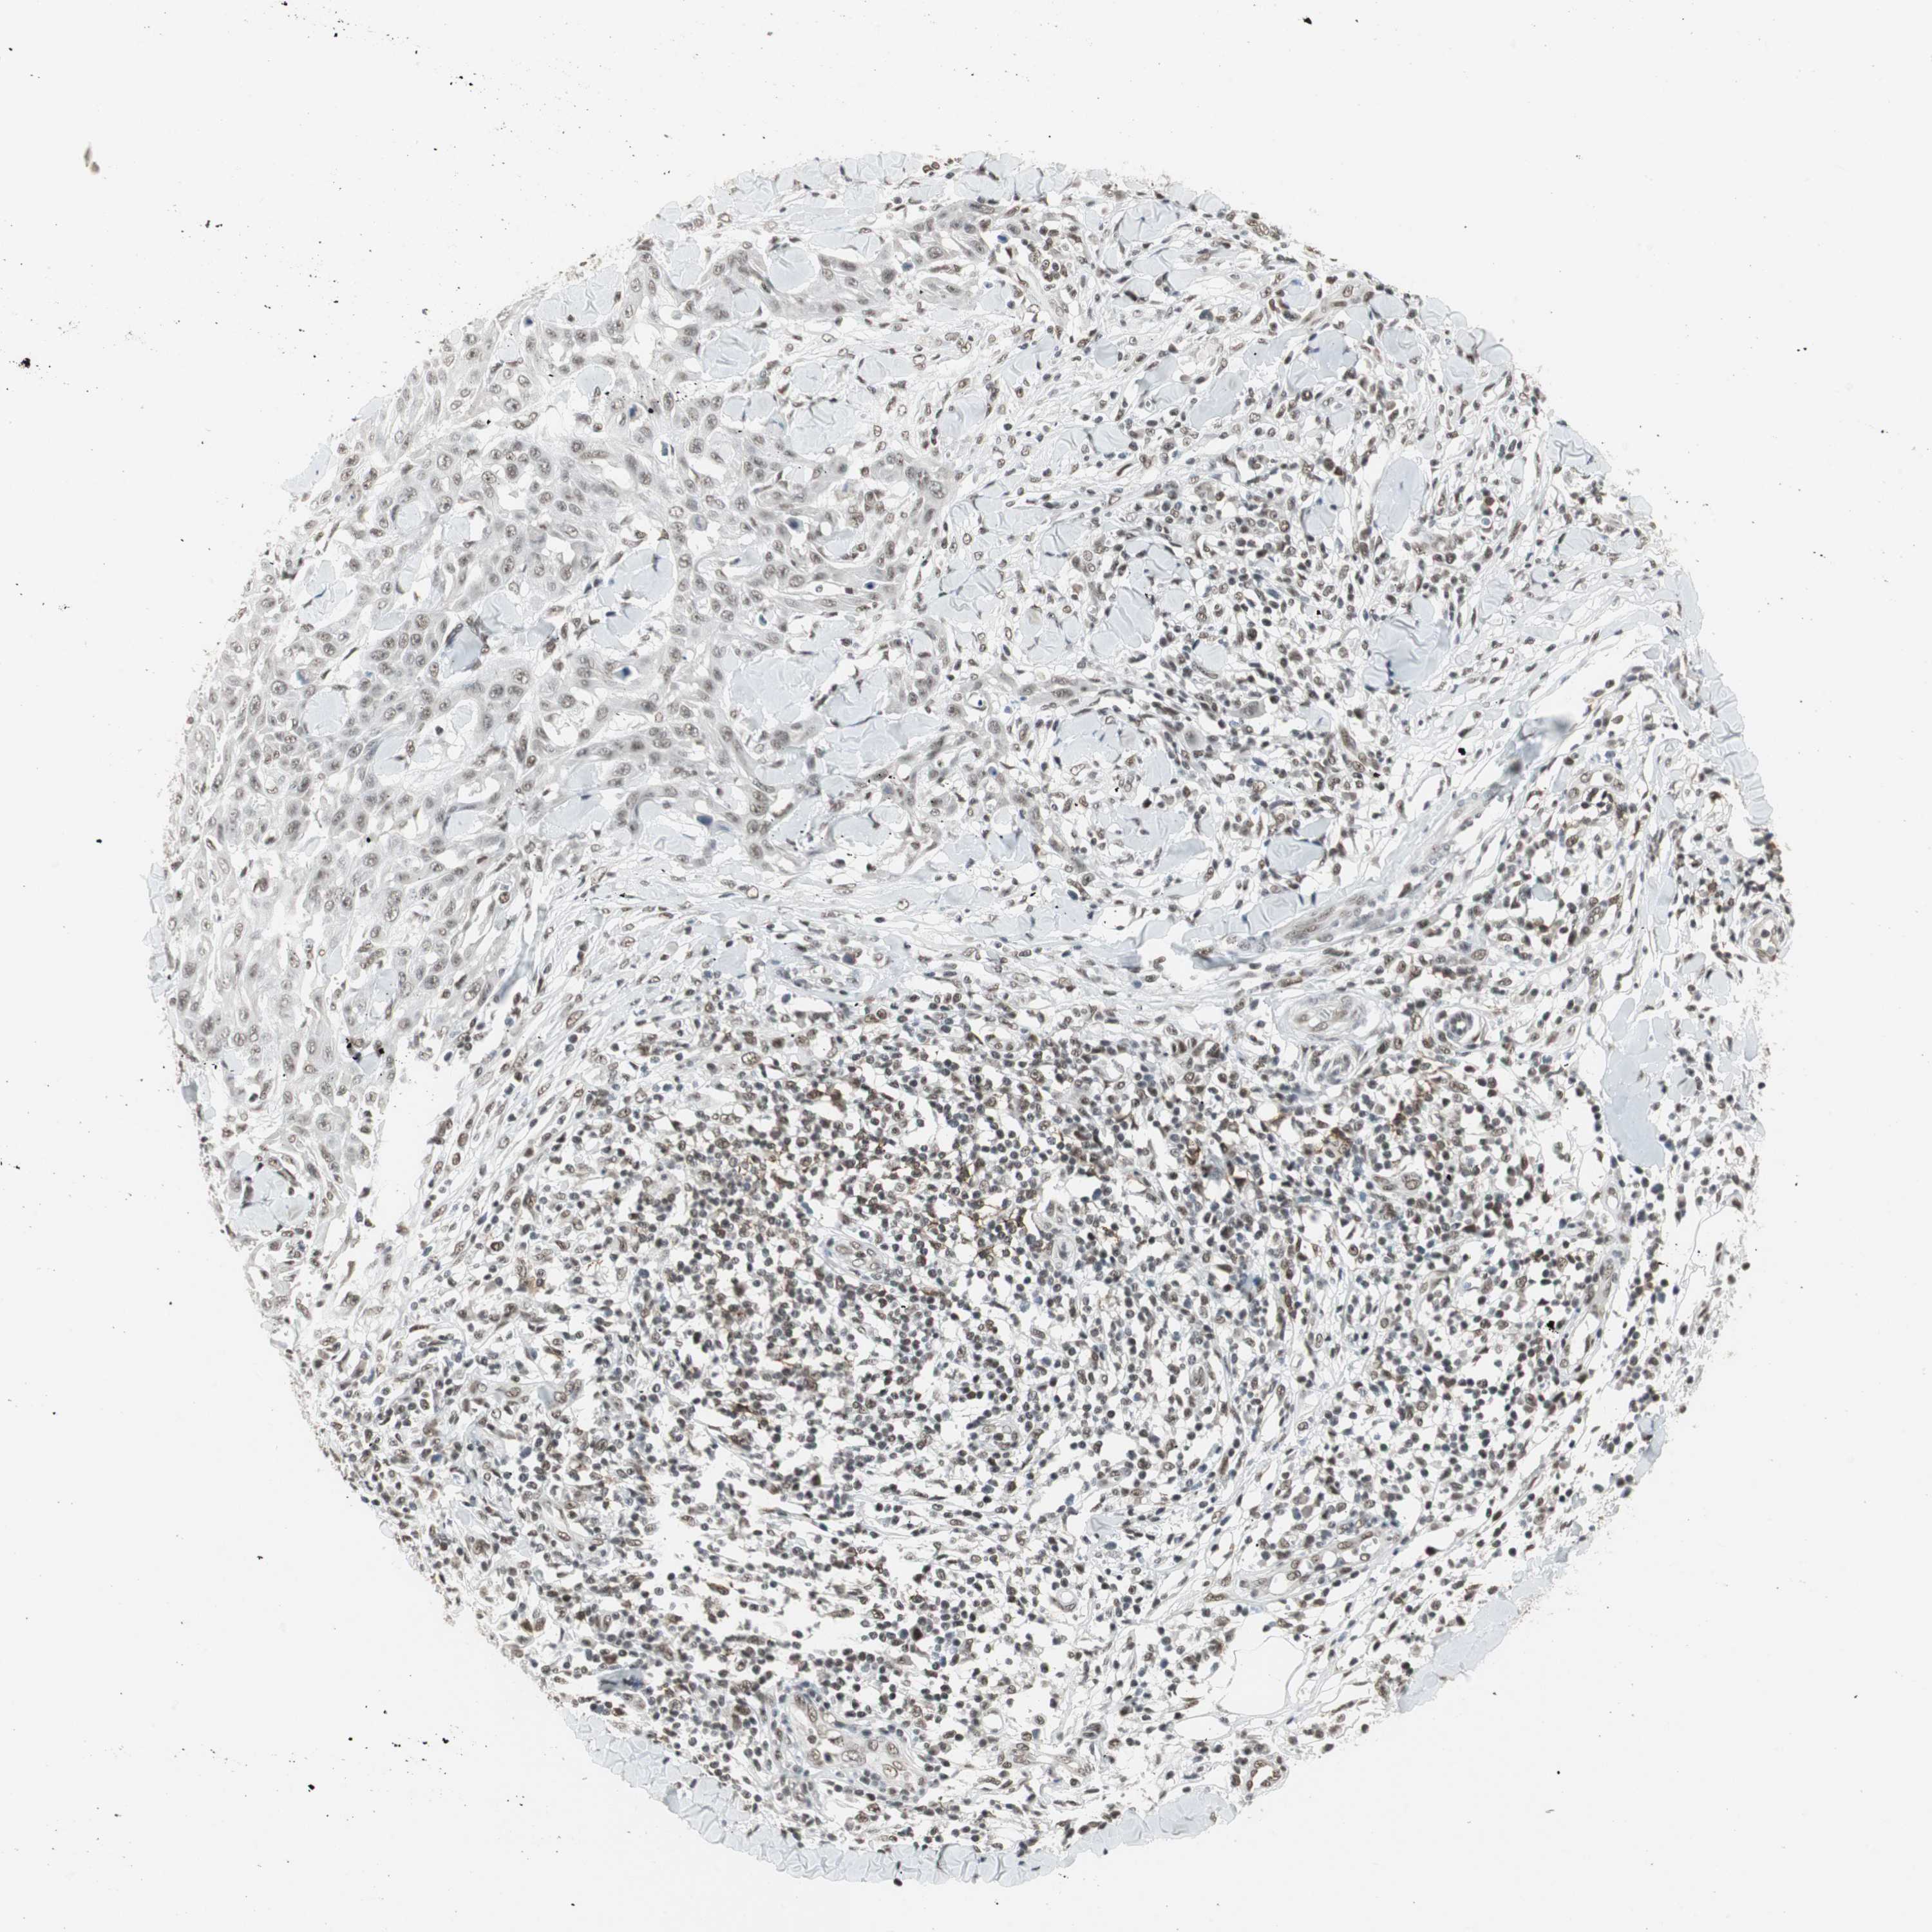

SKIN CANCER - Protein expressioni

A mouse-over function shows sample information and annotation data. Click on an image to view it in a full screen mode. Samples can be filtered based on level of antibody staining by selecting one or several of the following categories: high, medium, low and not detected. The assay and annotation is described here.

Antibody stainingi

Antibody staining in the annotated cell types in the current human tissue is reported as not detected, low, medium, or high, based on conventional immunohistochemistry profiling in selected tissues. This score is based on the combination of the staining intensity and fraction of stained cells.

Each image is clickable and will lead to virtual microscopy that enables deeper exploration of all samples and also displays staining intensity scores, fraction scores and subcellular localization as well as patient and tissue information for each sample.

Antibody CAB079946

Squamous cell carcinoma, NOS

Squamous cell carcinoma, metastatic, NOS